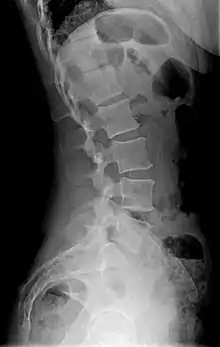

| Diagram showing normal curvature (posterior concavity) of the cervical (neck) and lumbar (lower back) vertebral column (spine) | |